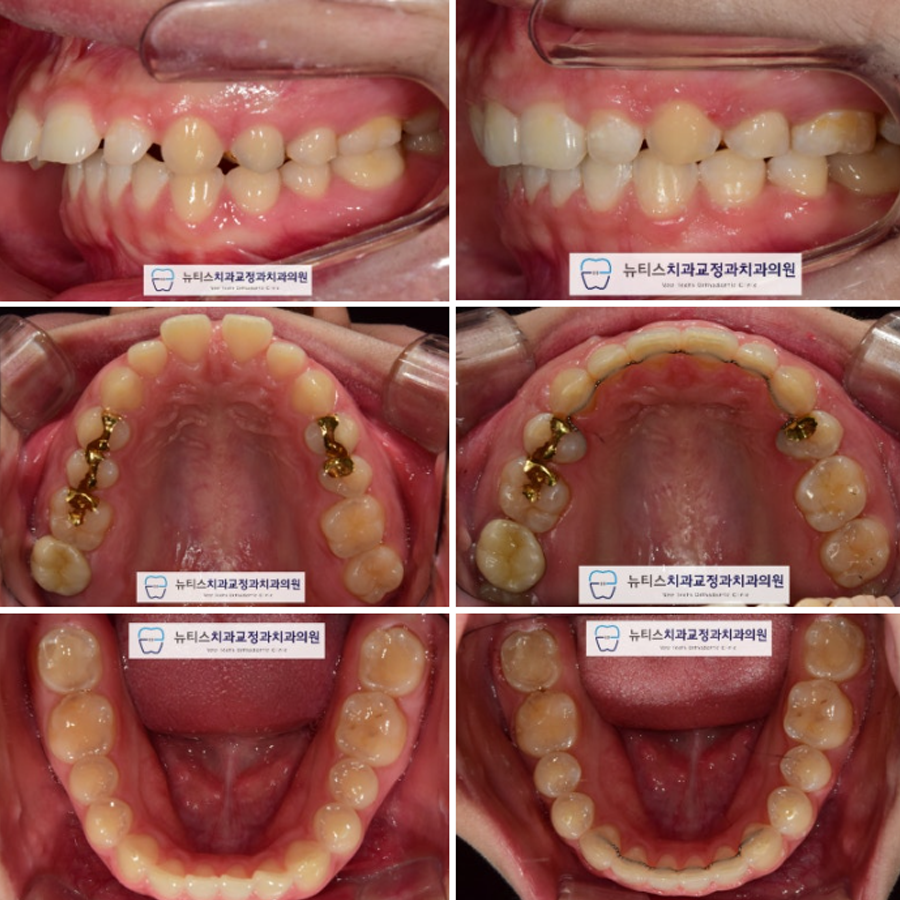

Ãø¸ð ¾È¸ð ¹× ¹æ»ç¼± »çÁøÀÔ´Ï´Ù.

µ¹ÃâµÈ ¾Õ´Ï°¡ µé¾î¿À¸é¼

µ¹ÃâÀÔµµ °³¼±µÇ¾ú½À´Ï´Ù.

Ä¡·á±â°£ : 1³â 9°³¿ù